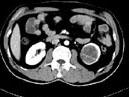

问题 女,63岁,左腰部隐痛不适1个月余,CT平扫+增强如图所示,下列哪项诊断正确 ( )

选项 A、左肾下极脓肿 B、左肾下极淋巴瘤 C、左肾下极错构瘤 D、左肾下极癌 E、左肾下极囊肿

答案 D